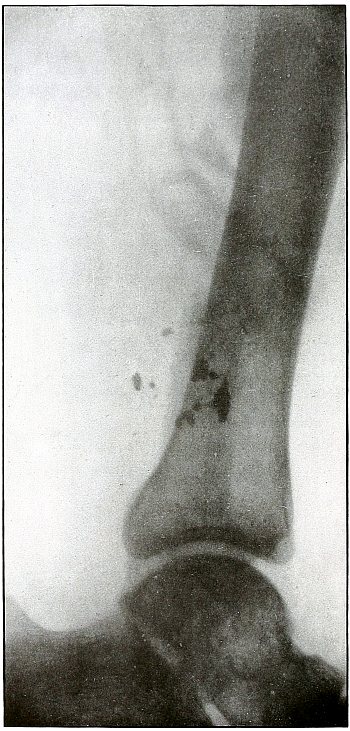

Gunshot fracture, ankle |

154 |